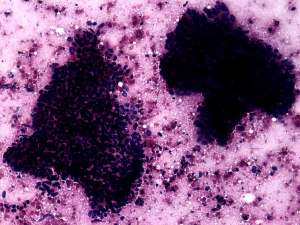

Cytology resulted in papillary cancer.

• The less obvious failure was my cytological diagnosis. Knowing the final diagnosis, of course, I would say otherwise. And re-examining the cytology sample later helped to avoid a similar mistake. Although the cytological picture resembles that seen in papillary cancer, the cytological pattern should raise colonic cancer. The clue is the palisading arrangement of tumor cells.